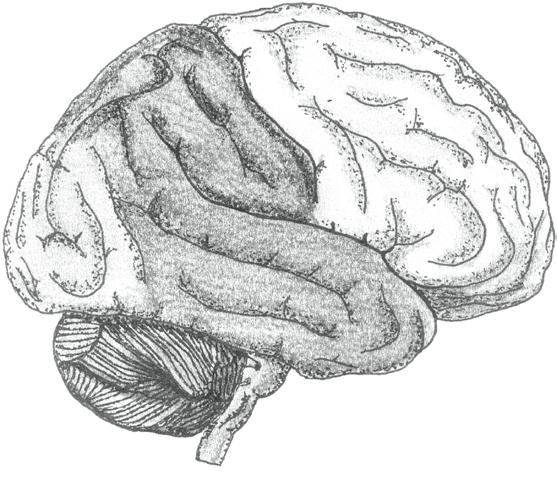

KONCOVÝ MOZEK (telencephalon) představuje nejobjemnější část lidského mozku. Je tvořen dvěma mozkovými polokoulemi (hemisperia cerebralia), které spolu velmi úzce spolupracují.

• Pravá mozková polokoule (hemisphera cerebri dextra) zpracovává především podněty s emočním doprovodem (včetně umění), chápe prostorové vazby, vládne představivostí.

• Levá mozková polokoule (hemisphera cerebri sinistra) reprezentuje zejména logické, matematické, analytické a technické myšlení a vládne také řečí.

Propojení obou polokoulí obstarávají mohutné svazky nervových vláken – mozkové komisury (commissurae cerebri). Největší komisurou je vazník neboli kalózní či bílé těleso (corpus callosum).

Vlastní hmota koncového mozku je členěna na šedou a bílou:

• Šedá hmota koncového mozku tvoří mozkovou kůru (cortex cerebri) na povrchu a podkorové struktury uvnitř hemisfér (sem patří např. bazální jádra a podkorové části limbického systému – jmenovitě amygdala a hipokampus).

• Bílá hmota koncového mozku leží v hloubce. Je tvořena gigantickým množstvím nervových vláken.

Povrch mozkových polokoulí je členěn řadou rýh a brázd do jednotlivých mozkových závitů – gyrů (gyri cerebri, jednotné číslo gyrus cerebralis). Popisujeme celkem pět mozkových laloků (lobi cerebri, jednotné číslo lobus cerebralis). Mozková kůra jednotlivých laloků obsahuje specifické korové oblasti (s jasně vymezenou funkcí) a dále asociační korové oblasti (které hrají roli propojovací, integrující a koordinující).

• Lalok čelní neboli frontální (lobus frontalis) je ve shodě se svým označením uložen v přední části mozku. Najdeme v něm mimo jiné oblast řízení motoriky (volní hybnosti včetně řízení produkce řeči a jemných pohybů očí) a korové oblasti čichu. Asociační oblast frontálního laloku (prefrontální kůra) zaujímá velký objem přední části frontálního laloku. Rozhodujícím způsobem ovlivňuje prožívání i chování, paměť a myšlení, motivaci i osobnostní charakteristiky

(včetně motivů, zájmů či kultivace chování a společensky adekvátních forem projevu s tlumením nevhodných a agresivních prvků). Vazba prefrontální kůry na psychické aspekty prožívání, chování a osobnosti člověka je nesporná.

• Lalok spánkový neboli temporální (lobus temporalis) ve svých neuronech zpracovává informace ze sluchového a rovnovážného čidla. Umožňuje porozumění řeči. Asociační oblasti se podílejí na mnoha funkcích včetně učení, paměti či chování.

• Lalok temenní neboli parietální (lobus parietalis) obsahuje především korové oblasti kožní citlivosti (senzitivity), chuti a dále asociační oblasti.

• Lalok týlní neboli okcipitální (lobus occipitalis) nese kromě asociačních oblastí zejména korové oblasti zrakové.

• Lalok ostrovní neboli inzulární (lobus insularis) je překryt lalokem spánkovým a jako jediný z mozkových laloků není na povrchu mozku vůbec patrný. Jeho funkce souvisí obzvláště s emočním prožíváním a řízením vnitřních orgánů a funkcí organismu.